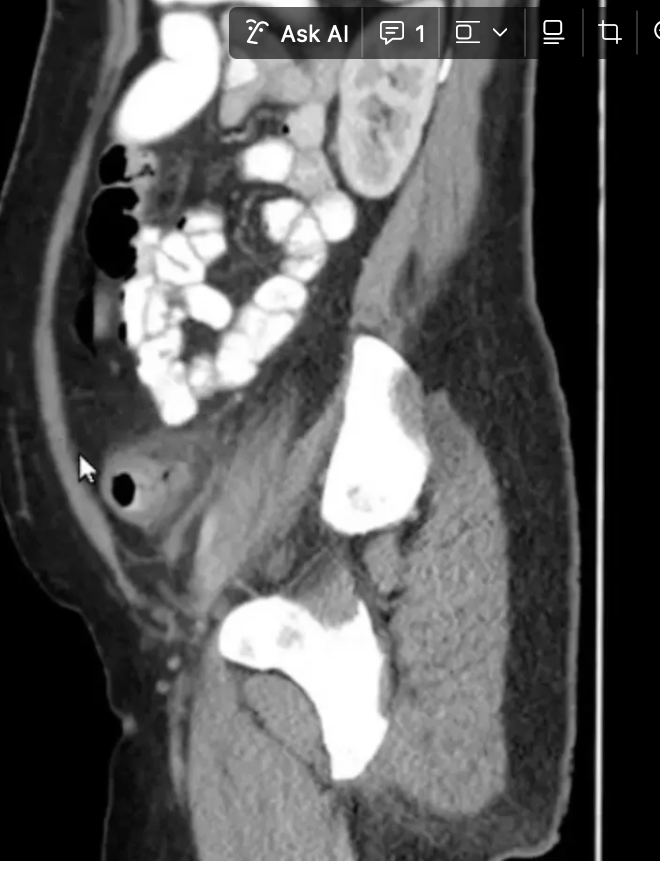

12

Q

Achado?

A

DIVERTÍCULO COM AR DENTRO DELE EM CÓLON DE PAREDE ESPESSADA E BORRAMENTO DE GORDURA

OS DIVERTÍCULOS SÃO AS BOLINAHS COM INTERIOR PRETO E AO REDOR BRANCO